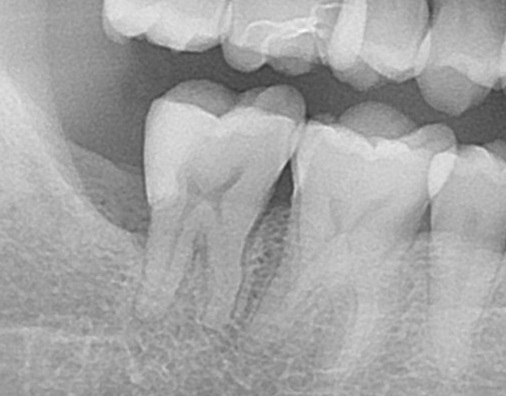

エックス線(レントゲン)写真を見てみると、

親知らずが横向きになっているのが分かります。

そして手前の歯にぶつかっています。

手前の歯に当たっている所が何やら黒くなってるのが分かりますでしょうか?

ここです。

ここが虫歯になっています。

1つ前のレントゲン写真と見比べると、赤枠の部分が黒く映っているのが分かりますね。

お口の中からは見えない部分なのですが、親知らずに物が詰まり、年月が経ち手前の歯を虫歯にしてしまいました。